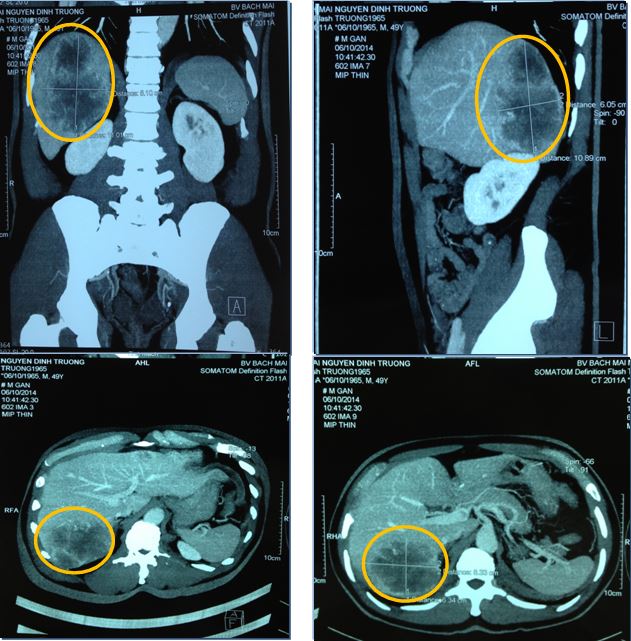

Chụp MSCT ổ bụng